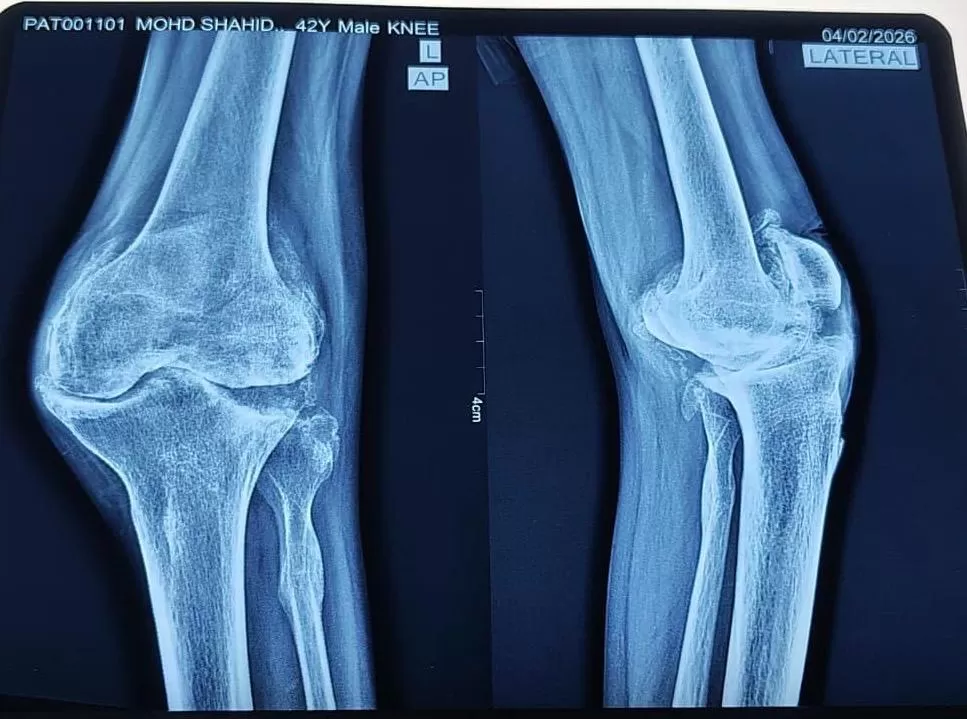

TKR (Total Knee Replacement)

Shahid

Name: Shahid

Date of Operation: 25 March 2026